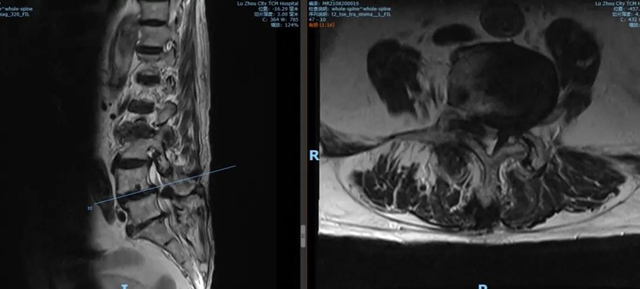

腰4 5 椎间盘 MRI